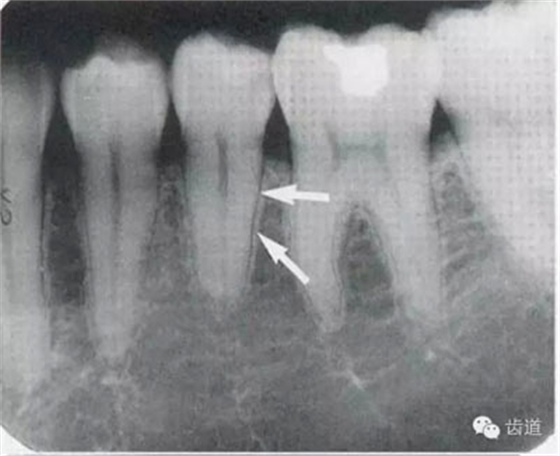

常見(jiàn)于下頜前牙區(qū),在牙根之間的牙槽骨內(nèi)并與牙長(zhǎng)軸平行的密度低的條狀影像。此為小血管進(jìn)入牙槽突的影像。

位于前磨牙根尖區(qū)域,為一大致圓形密度低的影像。頦孔位置變異大,多位于第二前磨牙根尖稍下,注意與根尖周病變區(qū)別,其要點(diǎn)是牙周膜及其骨硬板是否連續(xù)不斷。